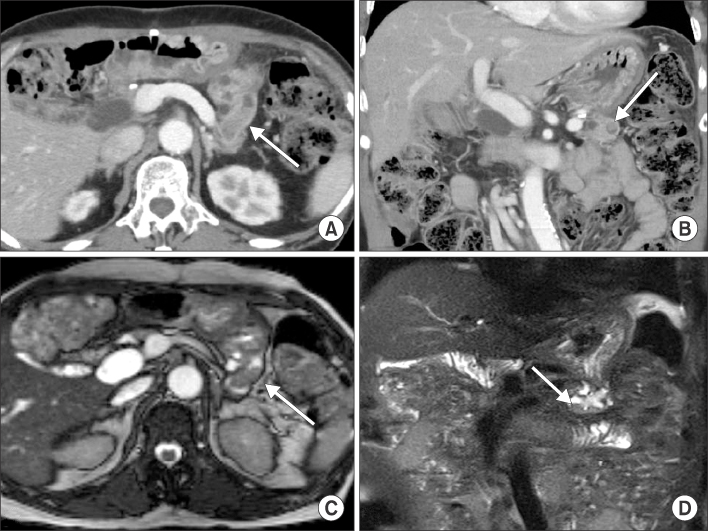

(A, B) Computed tomography (CT) findings after 47 months of resection. Axial and coronal CT scan shows diffuse pancreatic duct dilatation with enhancing mass (arrow) inside of the duct. (C, D) Magnetic resonance imaging findings after 47 month of resection. T2 weighted images also shows mass like lesion (arrow) inside of dilated pancreatic duct after 47 months of resection.

Fig. 3 (A, B) Computed tomography (CT) findings after 47 months of resection. Axial and coronal CT scan shows diffuse pancreatic duct dilatation with enhancing mass (arrow) inside of the duct. (C, D) Magnetic resonance imaging findings after 47 month of resection. T2 weighted images also shows mass like lesion (arrow) inside of dilated pancreatic duct after 47 months of resection.